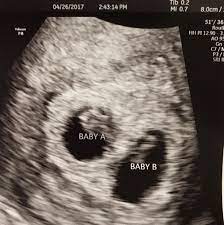

Confirming Multiple Gestations Using Ultrasound Empowered Women S Health

Confirming Multiple Gestations Using Ultrasound Empowered Women S Health from images.takeshape.io

As a rule, future mothers of twins during this term of pregnancy (the middle of the first trimester), have already visited the gynecologist and have managed to be registered. Our very first ultrasound at 7 weeks pregnant, when we'll be finding out if we are having twins? Details of the heart anatomy are not visible, but the atrial. Twins ultrasound @ 8 weeks. Ultrasound at 7 weeks pregnancy. Two healthy heartbeats can be seen! Early twin ultrasound at 7 weeks. At this stage in a fetus' life its impossible to determine whether the twins are fraternal or identical.

Twins can be diagnosed when ultrasound discovers more than one. Twins ultrasound @ 8 weeks. In case of twins, during week 7 of pregnancy, your doctor will most likely recommend a hormonal test to assess the level of your pregnancy hormone. Просмотров 227 тыс.5 лет назад. This sonogram was at 8 weeks and i am now 10 weeks, i have never felt so awful in my life!